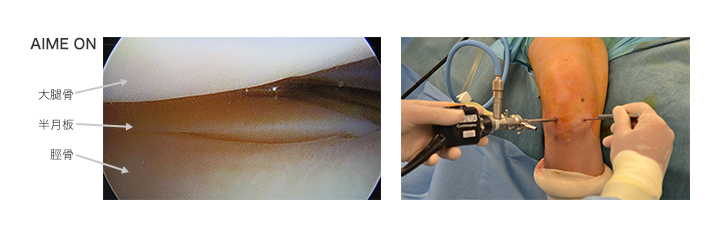

膝-knee-(土屋 明弘 先生)

A.I.M.E.画像処理への印象は?

膝の関節鏡手術において、術者の関心領域は画面上手前よりも奥側に多く存在し、そこの視認性があがるかどうかどうかが勝負となります。

例えば左の写真のように、手前付近に白い組織があるとそれがハレーションを起こしてしまい、見にくくなってしまうが、A.I.M.E.機能では、ハレーションが抑えられ、確認したい 箇所が見やすくなり、処置がしやすくなったと感じました。

また上の写真では少し分かりづらいですが、組織奥側が暗くて見えづらい場合など、難渋する症例が多いですが、A.I.M.E.画像処理では、奥の深いところも明るく見えました。重要な組織の境界部分の判断や処置方針の決定のための情報が得られやすくなり、即ち術者の手技の効率を高め、処置時間短縮の可能性が期待できそうです。

画像提供:船橋整形外科病院